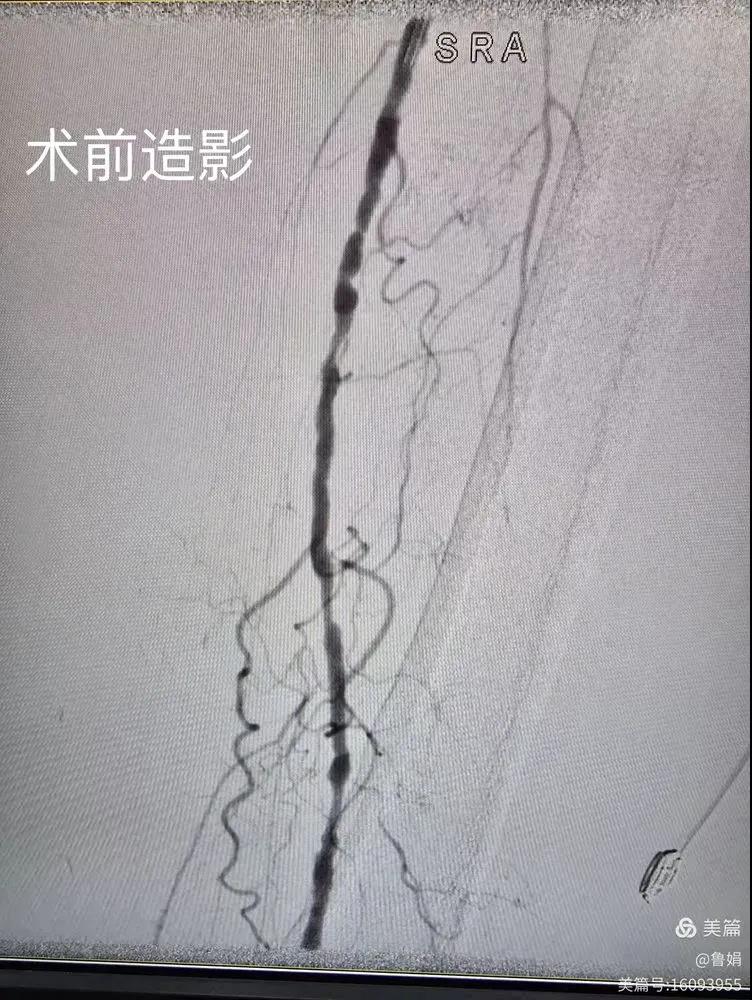

據(jù)悉,該患者,女,73歲,下肢動(dòng)脈硬化閉塞癥,“以靜息痛,間歇性跛行”入院,CTA評(píng)估:股淺動(dòng)脈,腘動(dòng)脈間斷性多段重度狹窄,外二科血管外科團(tuán)隊(duì)根據(jù)患者病情,結(jié)合檢查結(jié)果,經(jīng)過科室會(huì)診后,決定對(duì)該病人行介入治療。手術(shù)由周創(chuàng)業(yè)副主任與北大一院血管外科專家郭宏杰教授聯(lián)合開展,對(duì)股淺動(dòng)脈,腘動(dòng)脈重度閉塞段行血管開通+藥涂球囊擴(kuò)張成形,術(shù)后狹窄明顯緩解,血流恢復(fù)!

下肢動(dòng)脈閉塞的介入開通是外周介入領(lǐng)域難度最大的技術(shù)之一,這項(xiàng)微創(chuàng)介入手術(shù)的開展,實(shí)現(xiàn)了漯河市中醫(yī)院在下肢動(dòng)脈血管介入治療上零的突破,進(jìn)一步推動(dòng)了醫(yī)院介入治療技術(shù)的發(fā)展,讓患者足不出戶就能切實(shí)享受到優(yōu)質(zhì)的醫(yī)療資源,極大方便了患者就醫(yī)。(介入中心:魯娟)